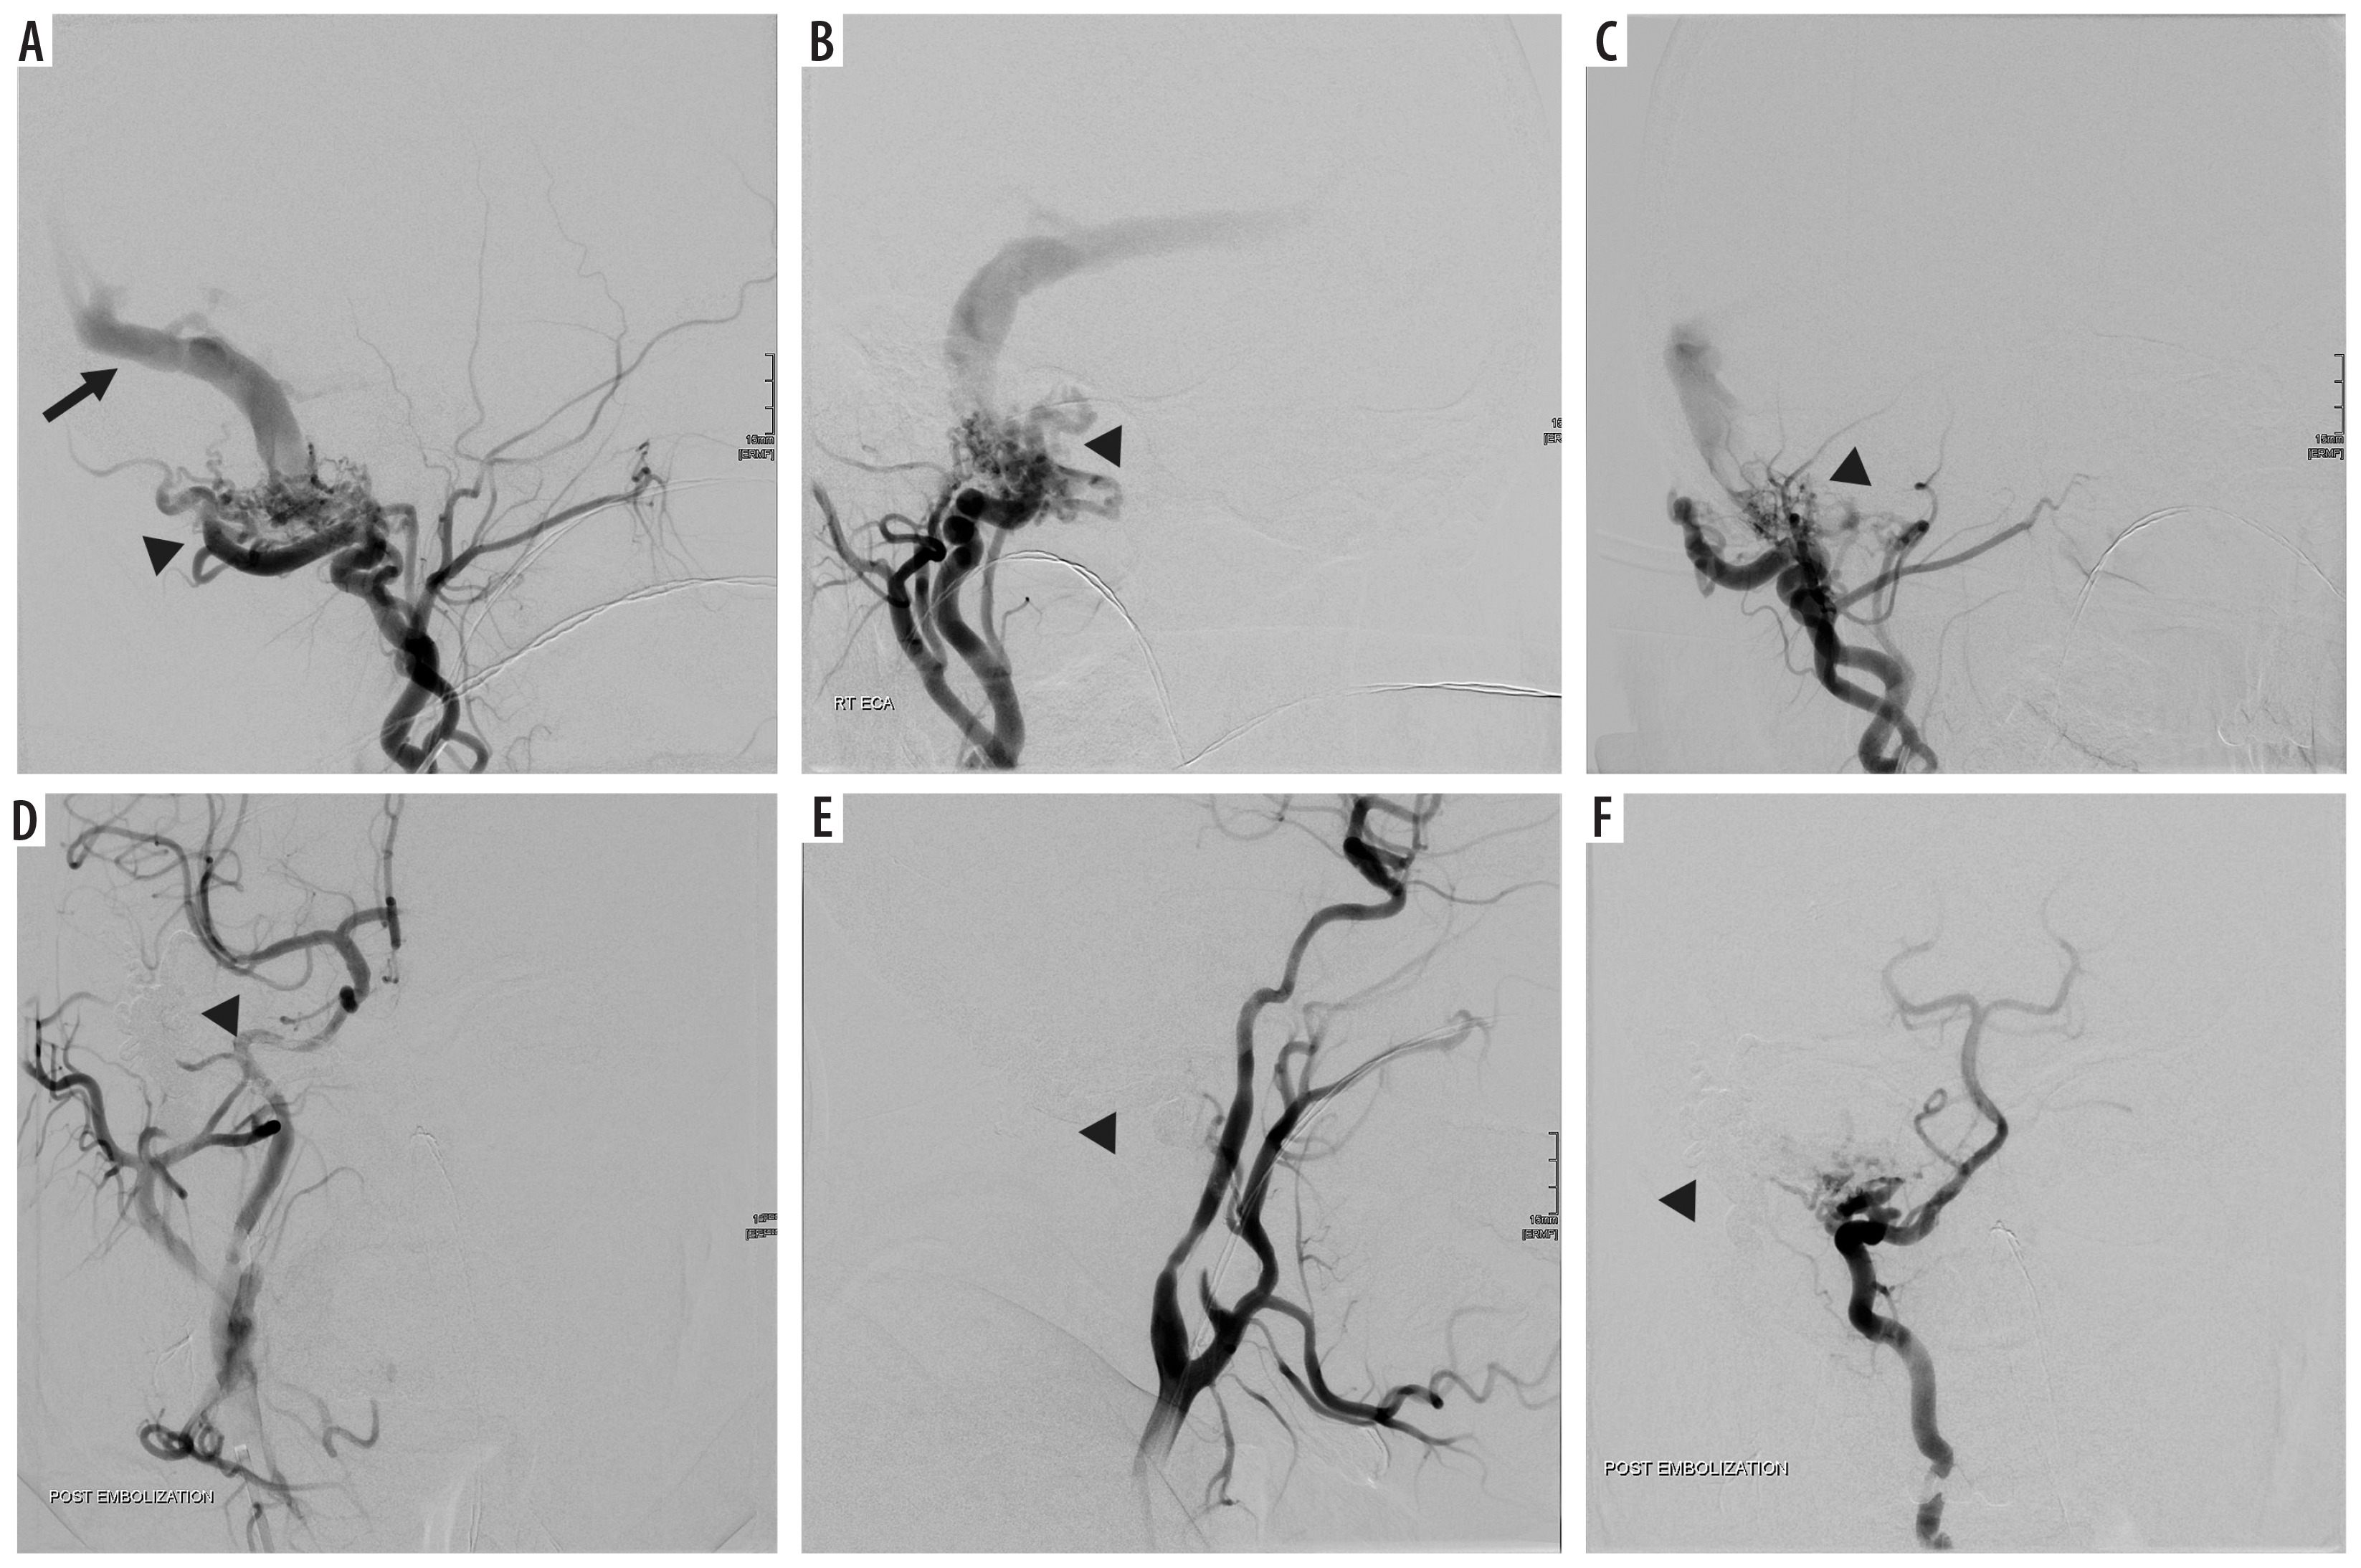

Figure 2

Digital subtraction angiography showing anterior dural arteriovenous fistula, between anterior segment of superior sagittal sinus and branches of bilateral temporal arteries, a few feeders of bilateral occipital arteries and ethmoidal branches of bilateral ophthalmic arteries (indicated by black arrowheads in images A-D). A branch of the left superficial temporal artery was cannulated distally with a microcatheter. Embolization was performed using ONYX (6cc). This caused maximum fistula closure. Subsequently, microcatheter cannulation of right temporal artery was also performed and embolization was performed using PVA 355-500. Post-embolization angiogram shows almost 90-95% embolization of the fistula occlusion (indicated by black arrowheads in images E-G)